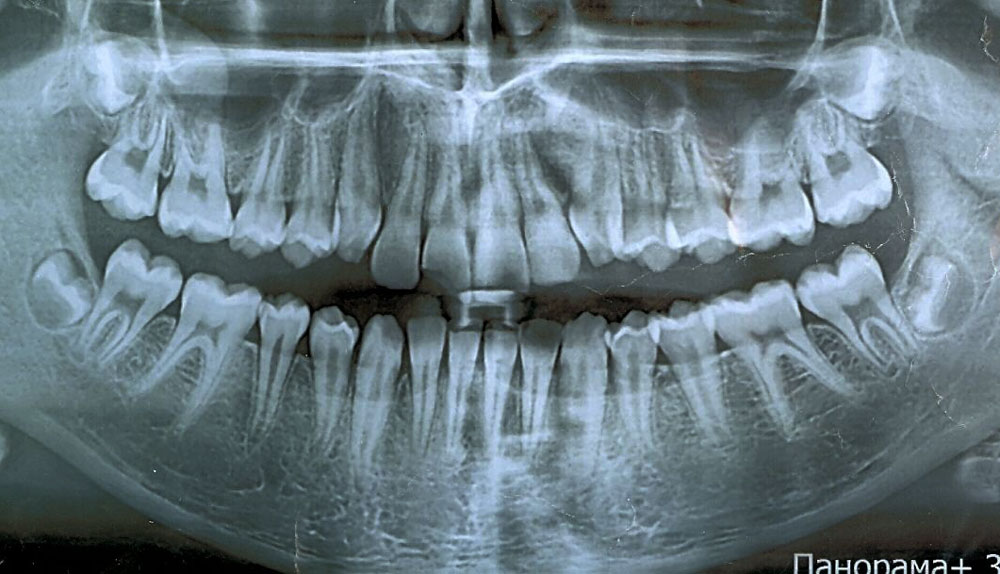

Панорама (ортопантомограмма, ОПТГ, панорамный снимок челюстей) – это обзорный круговой снимок зубов, при котором видна вся челюсть, развернутая в двухмерной плоскости. Она может быть цифровой и пленочной.

Панорамный снимок (или ортопантомограмма) – это плоское двухмерное изображение челюстей, зубов, гайморовых пазух и даже височно-нижнечелюстного сустава. Поскольку поверхность челюстей изогнутая, на плоской рентгеновской плёнке снимок отображается неравномерно увеличенным в боковых и передних отделах челюстей – то есть слегка деформированым.

- Много информации на одном снимке — видны все зубы с корнями, обе челюсти, гайморовы пазухи, височно-нижнечелюстные суставы, частично даже полость носа.

Панорамный снимок челюсти позволяет стоматологу получить изображение сразу всех зубов, включая верхнечелюстные суставы.

На рентгене отображаются зубные каналы, корни, костная ткань, пломбы и импланты.